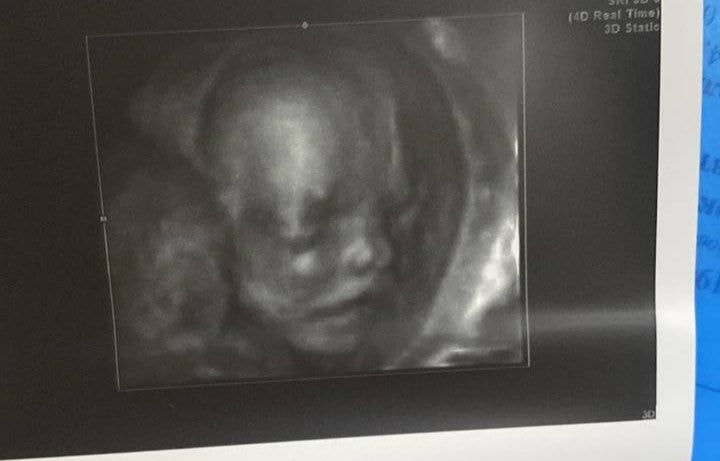

Веточка, Изображение

Веточка, спасибо) у тебя уже прям хорошо черты лица видно было у него) схожу тоже посмотрю на малыша своего тогда на днях)